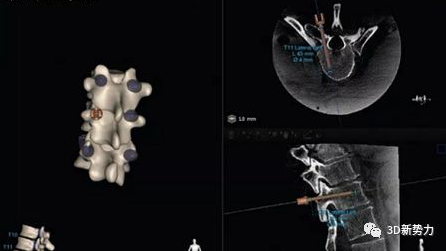

手术导航系统是近二十几年迅速发展的微创外科技术之一。它以核磁共振、CT 等医学影像数据为基础,在电脑上显示患者的内部情况。这样,医生手中的探针指向哪里,系统实时更新显示,让医生对手术器械在病人哪个解剖位置一目了然,使外科手术更快速、更精确、更安全。

图像引导外科系统最早应用于神经外科领域, 如神经外科颅内肿瘤的切除。近年来,随着图像引导相关技术的不断发展,其临床范围已逐步扩展到脊柱外科、耳鼻喉科(ENT)、整形外科、腹部外科、前列腺外科等。

脊柱外科如脊柱外科椎弓根钉植入、畸形矫正、 颈椎手术、关节置换等复杂的骨科手术;